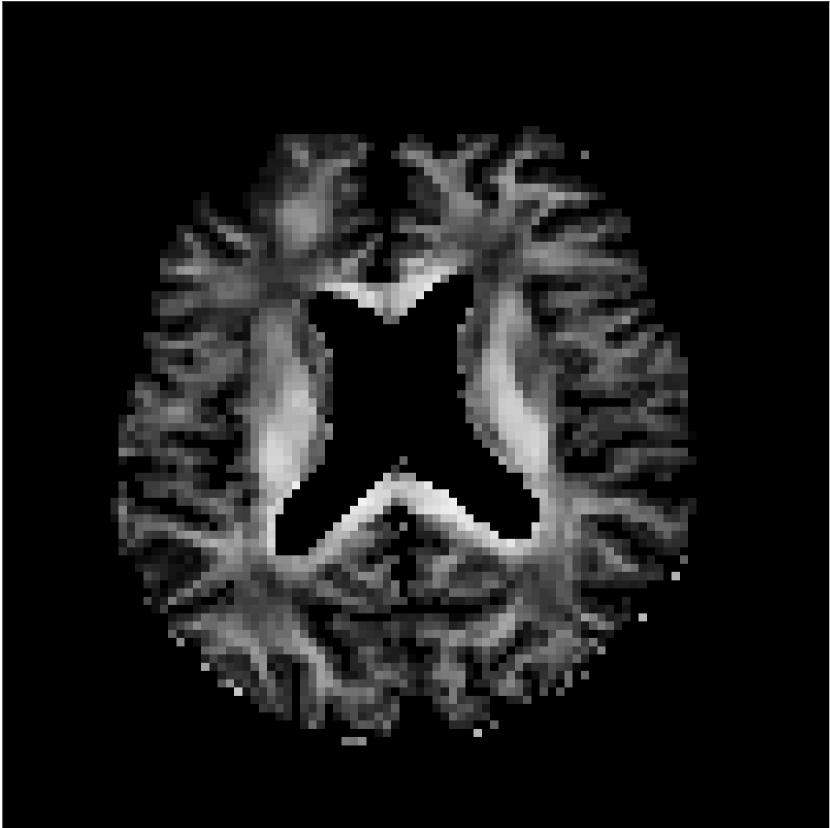

Figure 8 shows examples of non-diffusion-weighted images before and after processing. The raw images (Raw) served as the input for the magnitude deep learning (MCNN) and complex deep learning (CCNN) methods.

Raw 𝐱tsubscript𝐱𝑡\mathbf{x}_{t}

MCNN, fθ^(𝐱t)subscript𝑓^𝜃subscript𝐱𝑡f_{\hat{\theta}}\left(\mathbf{x}_{t}\right)

MCNN Resid., Ric(𝐱t)fθ^(𝐱t)Ricsubscript𝐱𝑡subscript𝑓^𝜃subscript𝐱𝑡\text{Ric}(\mathbf{x}_{t})-f_{\hat{\theta}}\left(\mathbf{x}_{t}\right)

CCNN, fθ^(𝐱t)subscript𝑓^𝜃subscript𝐱𝑡f_{\hat{\theta}}\left(\mathbf{x}_{t}\right)

CCNN Resid., Ric(𝐱t)fθ^(𝐱t)Ricsubscript𝐱𝑡subscript𝑓^𝜃subscript𝐱𝑡\text{Ric}(\mathbf{x}_{t})-f_{\hat{\theta}}\left(\mathbf{x}_{t}\right)

No PF

5/8 PF

Figure 8: Examples of non-diffusion-weighted images from in vivo data at b=0𝑏0b=0 s/mm2. Artifacts in the Raw image, 𝐱tsubscript𝐱𝑡\mathbf{x}_{t}, are corrected by the MCNN and CCNN models, fθ^(𝐱t)subscript𝑓^𝜃subscript𝐱𝑡f_{\hat{\theta}}(\mathbf{x}_{t}). Also shown are the residuals between the CNN corrections and the original Raw image with Rician bias correction Ric(𝐱t)Ricsubscript𝐱𝑡\text{Ric}(\mathbf{x}_{t}) [10]. The Gibbs artifacts removed by the methods are observed in the residuals. The MCNN method introduces some banding artifacts at the PF 5/8ths factor that are not present in the CCNN method.

Both methods remove artifacts, but the MCNN method allows residual rippling artifacts to pass through in the presence of partial Fourier. These rippling artifacts are not present in the CCNN method.